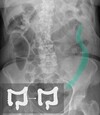

Imaging Studies

CT scan of abdomen and pelvis, abdominal MRI, or abdominal x-ray with barium swallow

Assess the extent and severity of disease as well as any complications (perforation, fistulas, abscess, stenosis)

Signs of intestinal inflammation: wall thickening with mucosal enhancement, distortion, and hyperintensity

Narrowing of the intestinal lumen giving a “string sign”